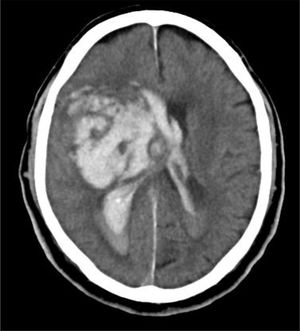

Caso 1Varón de 76 años con HTA, sin otros antecedentes de interés. Deterioro brusco del nivel de consciencia en su domicilio con un GSC de 4 (O1, V1, M2). Se activa código ictus y es intubado por el servicio de emergencias extrahospitalario. Al ingreso en el hospital, la TC craneal muestra hemorragia masiva de ganglios de la base izquierdos abierta a ventrículos, importante edema cerebral y signos de herniación cerebral (fig. 4). Valorado por el Servicio de Neurocirugía y UCI, ante la situación clínica y los hallazgos de la TC craneal, se descarta cualquier tipo de tratamiento. No existe documento de voluntades anticipadas. Se informa a la familia y se realiza la entrevista previa en el Servicio de Urgencias, aceptando el ingreso en la UCI con la exclusiva finalidad de la donación de órganos. Evolución a ME en 28h, siendo donante de hígado. El receptor hepático presentó buena evolución, siendo dado de alta de la UCI en el cuarto día postrasplante.